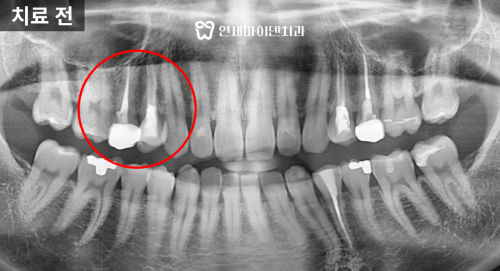

크라운 치료 전 상태

이번 케이스는 과거에 신경치료를 받은 후

크라운을 씌웠지만 시간이 지나면서

주변에 갭이 생기고

뿌리 끝에 염증이 생긴 케이스 였습니다.

크라운 경계가 충분히 덮이지 않아

치아를 제대로 보호하지 못하고 있는 상태였고,

내부 레진 코어 역시 오염 가능성이 있었기 때문에

크라운 교체와 함께 재신경치료를 진행하게 되었습니다.